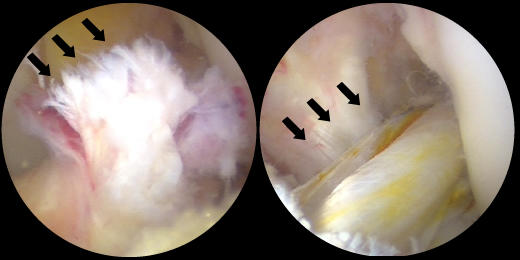

左:損傷した前十字靭帯(黒矢印)右:再建された前十字靭帯(黒矢印)

正常な内側半月板(黒矢印)

左:損傷して前方に逸脱した外側半月板(黒矢印)

右:半月板縫合術後(黒矢印)前方に逸脱した外側半月板を整復し縫合した。